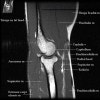

팔꿈치 관절의 MRI 단면 영상

4. MR Arthrography : Useful for evaluation of the collateral ligaments and cartilage surfaces.

5. Elbow Arthrography : UCL pathology in throwers, Osteochondral lesions and repair, Loose bodies